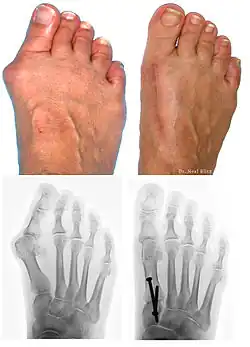

A bunion, also known as hallux valgus, is an outward deformity of the foot's metatarsophalangeal (MTP) joint which connects the big toe to the foot.[2] The rear tarsametatarsal joint that holds the metatarsal bone in a straight-ahead position weakens, the metatarsal moves outward plus rotates 90 degrees bringing the sesamoids up against the adjacent toe. This results in the head of the metatarsal bulging outward, and the big toe then bends inward toward the other toes. The joint often becomes red and painful due to rubbing in a cramped shoe.[2] The onset of bunions is typically gradual.[2] Joint complications may include bursitis or arthritis.[2] A similar condition of the little toe is referred to as a bunionette.[2]

Bunions can be diagnosed and analyzed with a simple x-ray, which should be taken with the weight on the foot.[10] The hallux valgus angle (HVA) is the angle between the long axes of the proximal phalanx and the first metatarsal bone of the big toe. It is considered abnormal if greater than 15–18°.[11] The following HV angles can also be used to grade the severity of hallux valgus:[12]

- Mild: 15–20°

- Moderate: 21–39°

- Severe: ≥ 40°

The intermetatarsal angle (IMA) is the angle between the longitudinal axes of the first and second metatarsal bones, and is normally less than 9°.[11] The IM angle can also grade the severity of hallux valgus as:[12]

- Mild: 9–11°

- Moderate: 12–17°

- Severe: ≥ 18°